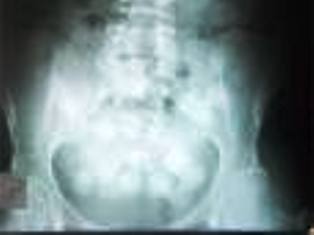

Hastanede rötgeni çekilen Olmedotorrs’ın karnında esnek bir cisim içinde uyuşturucu paketlerinin bulunduğu tespit edildi. Hastanede yapılan müdahale sonrası Olmedotorrs’ın karnından çıkartılan prezervatif içindeki uyuşturucu paketleri görenleri hayrete düşürdü. Ankara Esenboğa Havalimanı’nda ilk kez böyle bir olaya şahit olduklarını belirten yetkililer, bundan sonra önlemlerin daha da artırılacağı bilgisini verdi.